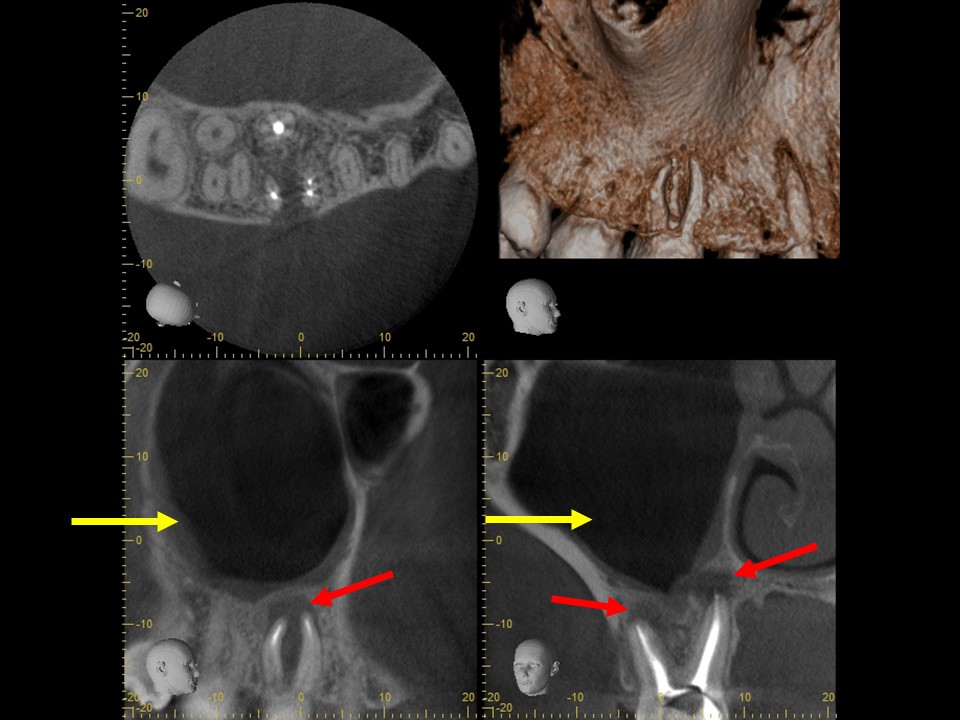

Case3 歯性上顎洞炎のケース

診断と治療計画の立案

右上の6番の大臼歯に、大きなコンポジットレジン充填がしてありました。レントゲンおよびCT診査を行ったところ、歯髄に達する大きな充填の跡が見られ、根尖部の骨はすでに大きく溶けて吸収しており、炎症は副鼻腔に達していました(下写真)。レントゲンおよびCT画像から、虫歯治療後の歯髄壊死・壊疽から生じた慢性化膿性根尖性歯周炎と診断しました。また、根尖病変に起因する歯性上顎洞を併発していると診断しました。

治療前レントゲン | 治療前CT |

治療前レントゲン |

治療前CT |

治療前のレントゲンおよびCT画像です。右上6番には歯髄に達する大きなコンポジットレジン充填がされています。

根尖部の骨は黒く大きく溶け(赤矢印)、ほぼ上顎洞と交通しています。

上顎洞内部は上方までX線不透過性が亢進し(白くなっています)、典型的な上顎洞炎の像を呈しています(黄矢印)。